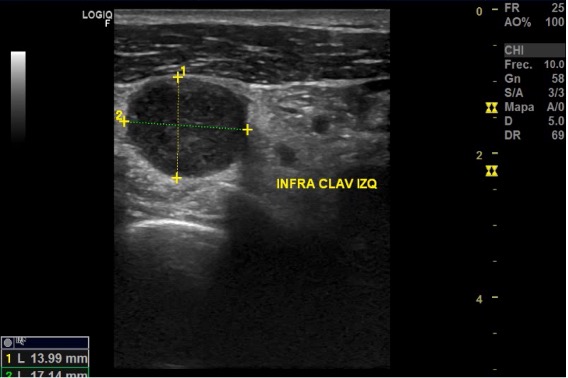

Ecografía: Conglomerado adenopático en axila izquierda. Adenopatía más grande (30 x 40 mm) hipoecogénica, redonda con pérdida del hilio graso, de aspecto infiltrativo y con captación Doppler. Adenopatías infraclaviculares de 27,5 x 12,2 y una glomerulación de 13,9 x 17,1 mm hipoecogénicas con pérdida de estructura normal. Adenopatías perihiliares hepáticas de 9 x 23 mm y otro 26 x 17; perihiliar esplénica de 12 x 4 x 5 mm, e inguinal izquierda de 9,3 x 7,8 mm.